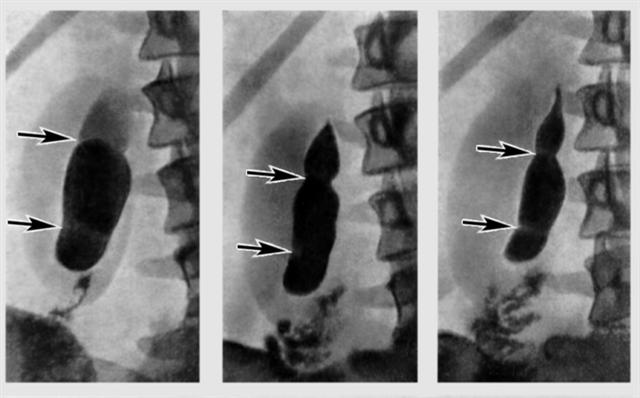

Рис. 2. Серия холецистограмм после стимуляции желчеотделения при множественных врожденных перетяжках желчного пузыря (указаны стрелкой): форма пузыря в процессе его сокращения не изменяется.